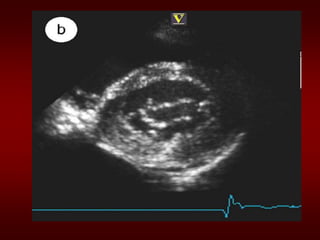

Evaluation of MS

• ECG: may show atrial fibrillation and LA

enlargement

• CXR: LA enlargement and pulmonary

congestion. Occasionally calcified MV

• ECHO: The GOLD STANDARD for

diagnosis. Asses mitral valve mobility,

gradient and mitral valve area